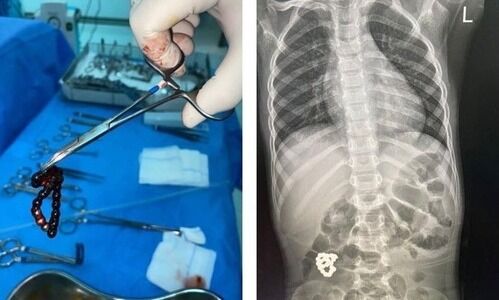

മേപ്പാടി: പിഞ്ചുകുഞ്ഞിന്റെ വയറ്റിൽ പോയ സേഫ്റ്റി പിൻ വിജയകരമായി പുറത്തെടുത്തു. കാട്ടിക്കുളം...

ജുബൈൽ: സൗദിയിൽ ആറ് വയസ്സുള്ള കുട്ടിയുടെ വയറ്റിൽനിന്ന് അപകടരമായ നിലയിൽ കണ്ടെത്തിയ ബ്രേസ്ലെറ്റ് പുറത്തെടുത്തു....